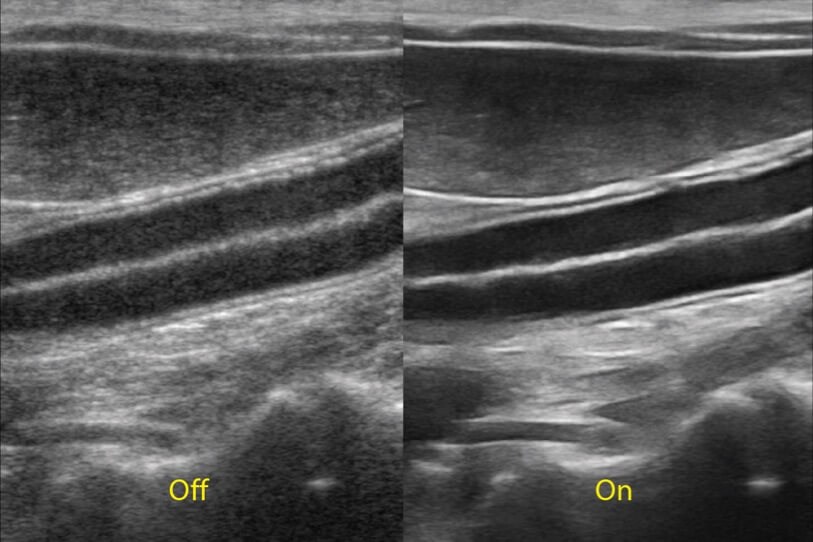

ProPet 70 進(jìn)一步提升了微米成像算法,更加注重對基礎(chǔ)原始圖像的還原和保留,在有效減少斑點(diǎn)噪聲、增強(qiáng)組織邊界顯示的同時(shí),避免過度優(yōu)化丟失真實(shí)的解剖信息。

增強(qiáng)穿刺針在動物解剖結(jié)構(gòu)中的位置,提高穿刺介入的安全性和準(zhǔn)確性。